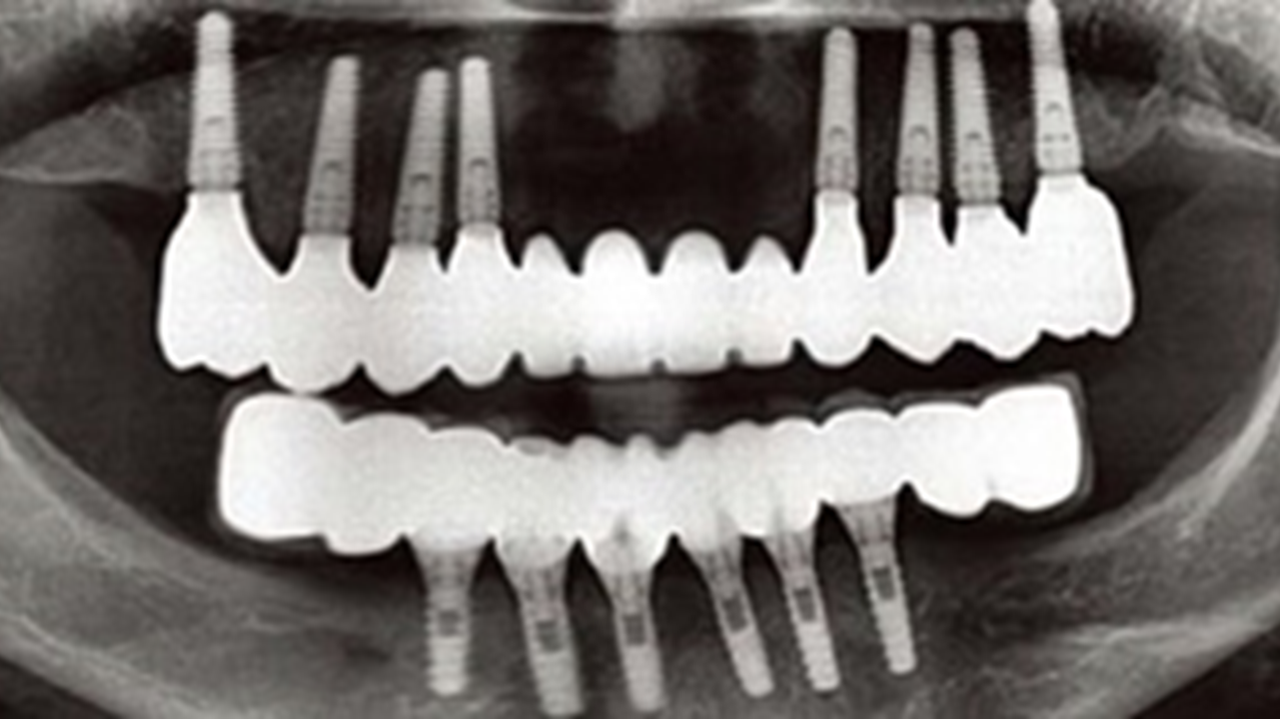

Clinical case: Advantage of fuse abutment with AnyRidge implant for immediate loading in

upper fully edentulous case

“AnyRidge shows excellent initial stability

& stable results after immediate loading in

upper fully edentulous case. ”

Clinical case: Extraction of all teeth in upper maxilla,

immediate implant placement, & provisionalization